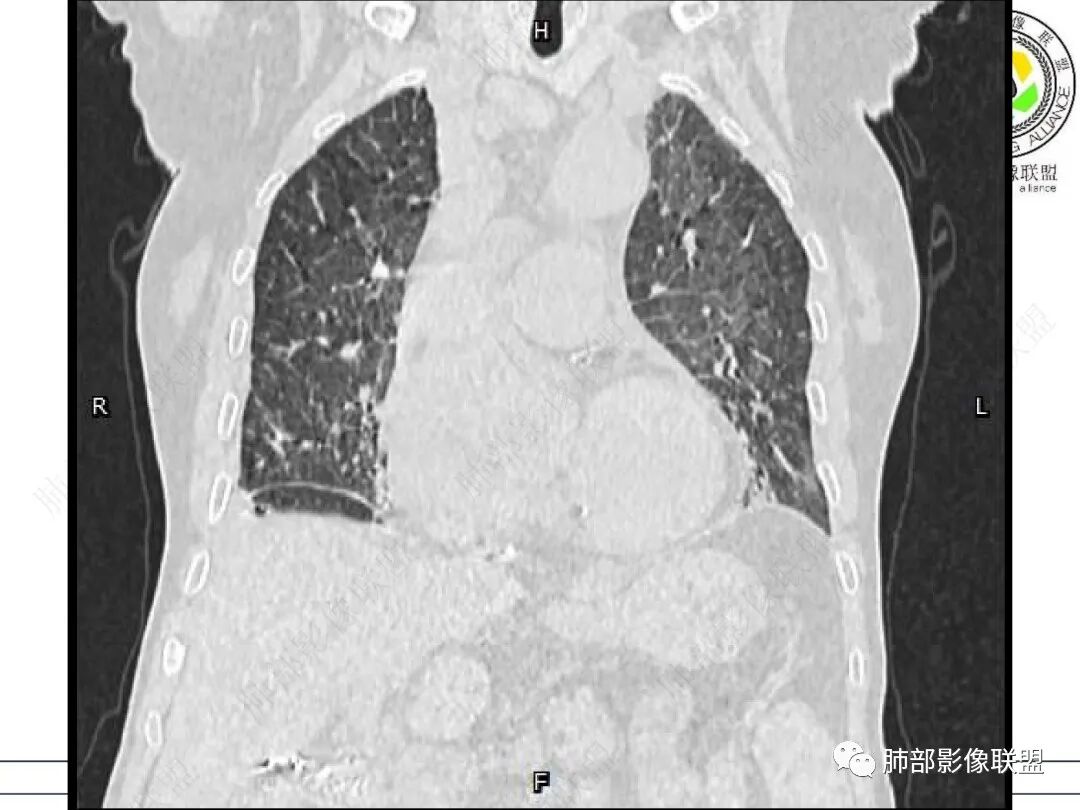

心脏大,胸腔积液,小叶间隔增厚,双肺磨玻璃影,考虑存在肺水肿,另双肺间质性炎性,类风关病史,考虑CTD-ILD,左肺上叶结核可能。

老年女性,类风湿关节炎病史多年。发热。以两肺下叶为主弥漫磨玻璃及网格状透亮影,透亮度减低,局部小蜂窝状改变;两肺胸膜下散在几枚实性病灶;双侧胸腔积液。考虑RA-ILDNSIP

女,71,外阴疼痛2周,发热1周。类风关、高血压、高血糖、卵巢囊肿、肠粘连、胆囊结石等病史及相关药物治疗史。胸部CT:两肺弥漫磨玻璃,血管束增粗,两下肺后肋膈角多发蜂窝,对称分布,双侧胸腔少量积液,纵隔窗心脏大血管影明显增宽。考虑混合性病变,CTD-ILD,并肺水肿?并PJP?。

GGO重力趋势明显,PJP重力趋势没这么明显

GGO重力趋势明显,双侧胸腔积液,还是比较支持肺水肿类病变。

①影像表现复杂:较弥漫间质性改变,对称磨玻璃密度为主,小叶间隔增厚,有一定重力分布趋势,未见明显纤维化,气囊及蜂窝位于肺边缘,未见典型“月弓征”。心脏影增大,双侧胸腔积液。

患者存在肺水肿应当是合理的解释。其他旁证还有,心脏影增大,肾小球滤过率降低,双侧胸腔积液等等……